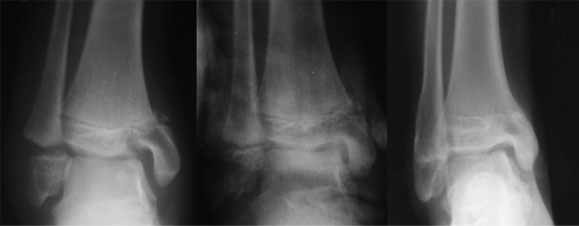

The xray picture shows one of the most common causes of deformity i.e. injury to the epiphysis(growth plate). As the growth plate heals it fuses and the growth arrests causing deformity.